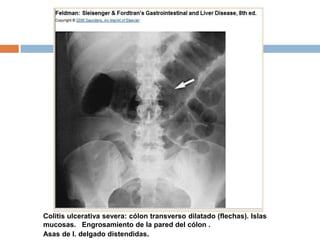

 Megacolon tóxico : colon transverso con

diámetro >5 a 6 cm, con pérdida de

haustraciones en los pacientes con crisis

graves de CU.

Colitis ulcerativa severa: cólon transverso dilatado (flechas). Islas

mucosas. Engrosamiento de la pared del cólon .

Asas de I. delgado distendidas.